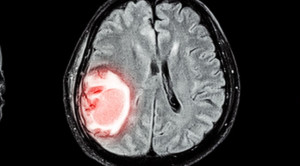

Cara membaca atau interpretasi rontgen toraks (chest x-rays) memerlukan pengertian anatomi dan fisiologi dari organ dada serta pengertian akan limitasi dari pemeriksaan...(Baca Selengkapnya)